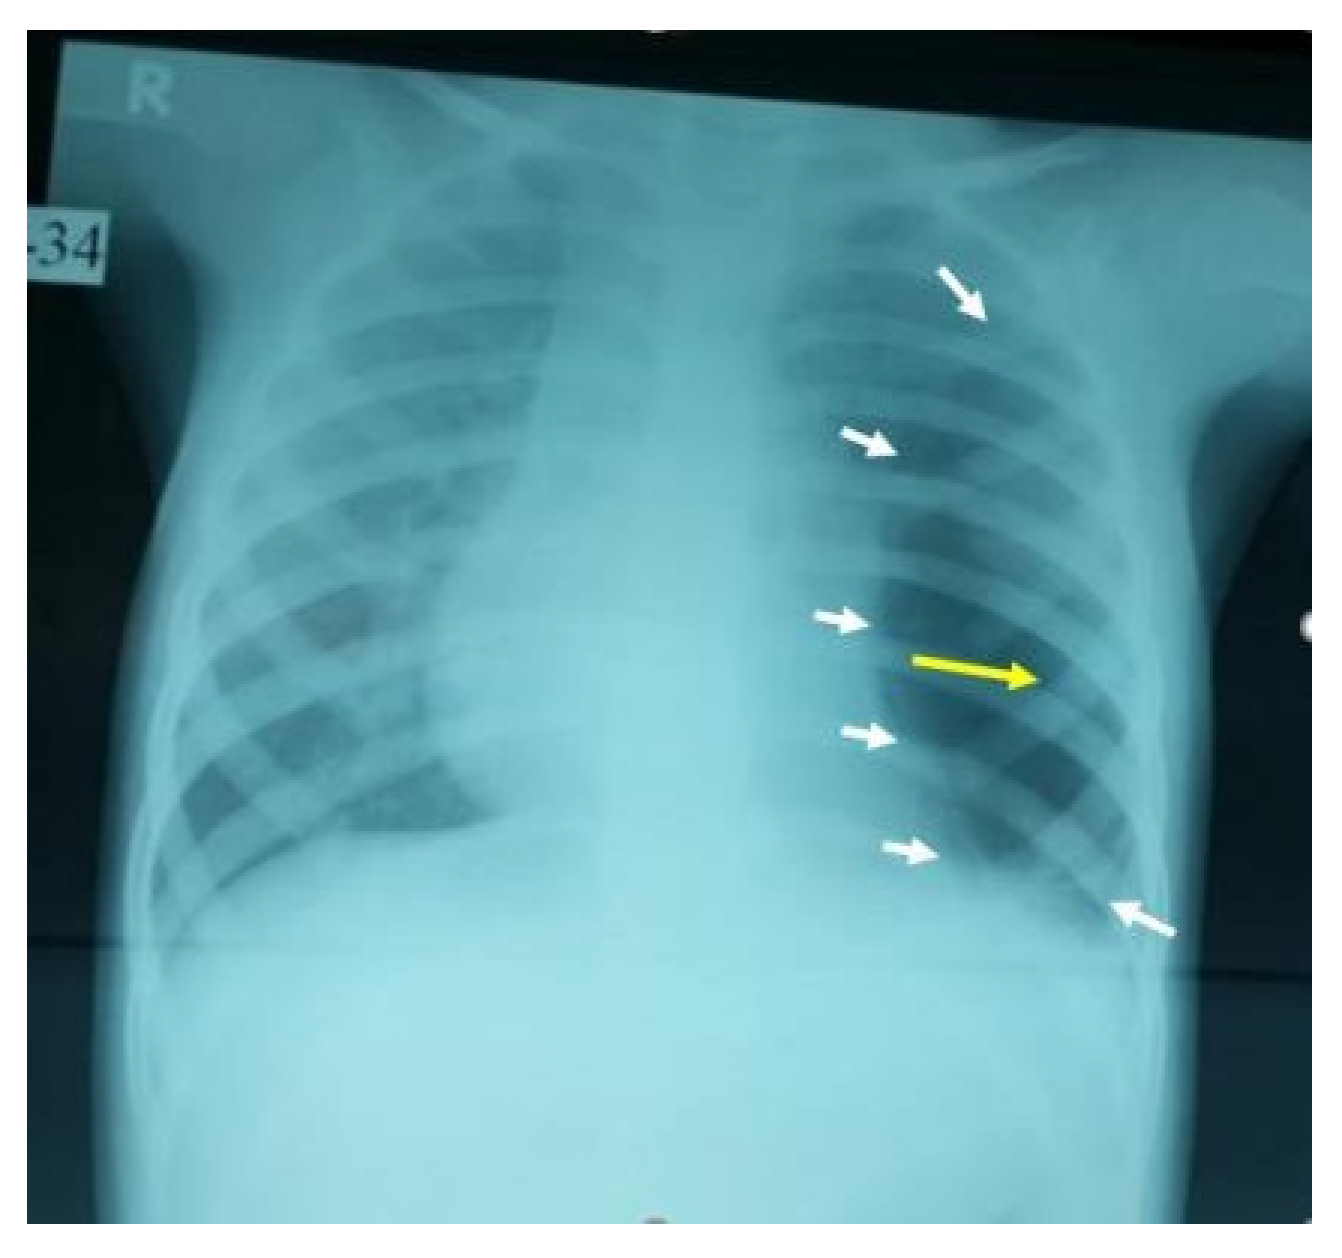

Figure 1. Large left-side cavity with a thick wall filled with thick fluid, with a clear fluid, with a clear fluid level occupying more than 80% of the left-sided lung. The arrows are pointing to the boundaries of the fluid level with mild compression of the mediastinum to the other side and secondary hyperinflation of the right lung.

Figure 2. This AP film X-ray shows a large cystic cavity with a marked attenuated vascular marking on the left middle and lower zone, with a clear compression on the heart and ipsilateral hemidiaphragm, raising the possibility of congenital cavity lung lesion, especially CPAM-1 (the white arrows show the borders of the cyst, while the yellow arrow points to the center of the cavitation).

A 3-year-old girl was referred from Najran hospital for further evaluation of complicated pneumonia. She was fully vaccinated, thriving, and had had a recent chest infection several weeks back. She presented with fever, and shortness of breath for a week. On physical exam, she was ill and febrile, with markedly reduced breath sounds on the left side. She had no clubbing as well as no organomegaly but had a good BCG scar. On admission, the chest X-ray showed a large left-sided lung abscess (Figure 1). Previous chest films were retrieved and showed hyperlucency and a large cavity on the left side of the lung, suggesting congenital pulmonary airway malformation (CPAM)-1 (Figure 2). Blood work showed marked leukocytosis with a left-sided shift and very high acute-phase reactant (CRP, ESR), along with negative blood and sputum cultures. The chest CT confirmed the diagnosis of lung abscess and CPAM-1 with no evidence of feeding vessels to the left lower lobe. Lymphocyte subset analysis was not requested, as we believed the primary cause was related to lung malformation. As the patient was initially sick with a large lung abscess, she was managed as a patient with a lung abscess secondary to CPAM-1 and received 4 weeks of IV therapies (vancomycin and meropenem) based on the infectious disease team’s recommendation, which matched our local guideline. She was then scheduled for lobectomy of the left lower lobe. The patient had a smooth course of recovery with no reported complications and completed 8 weeks of antibiotic therapy.